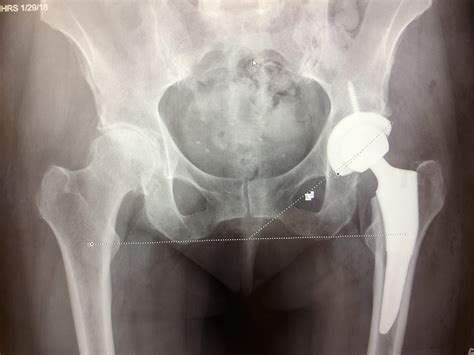

• Preoperative Preparation: Patients undergo a thorough evaluation, including medical history, physical examination, and imaging tests like X-rays or MRIs. Preoperative planning ensures that the surgery is tailored to the patient’s specific needs.

• Removal of the Femoral Head: The damaged femoral head is removed, and the remaining bone is prepared to accept the prosthetic implant.

• Implant Placement: The prosthetic femoral head is attached to the remaining femoral shaft using a stem. The stem can be cemented or press-fit into the bone, depending on the patient’s bone quality and the surgeon’s preference.